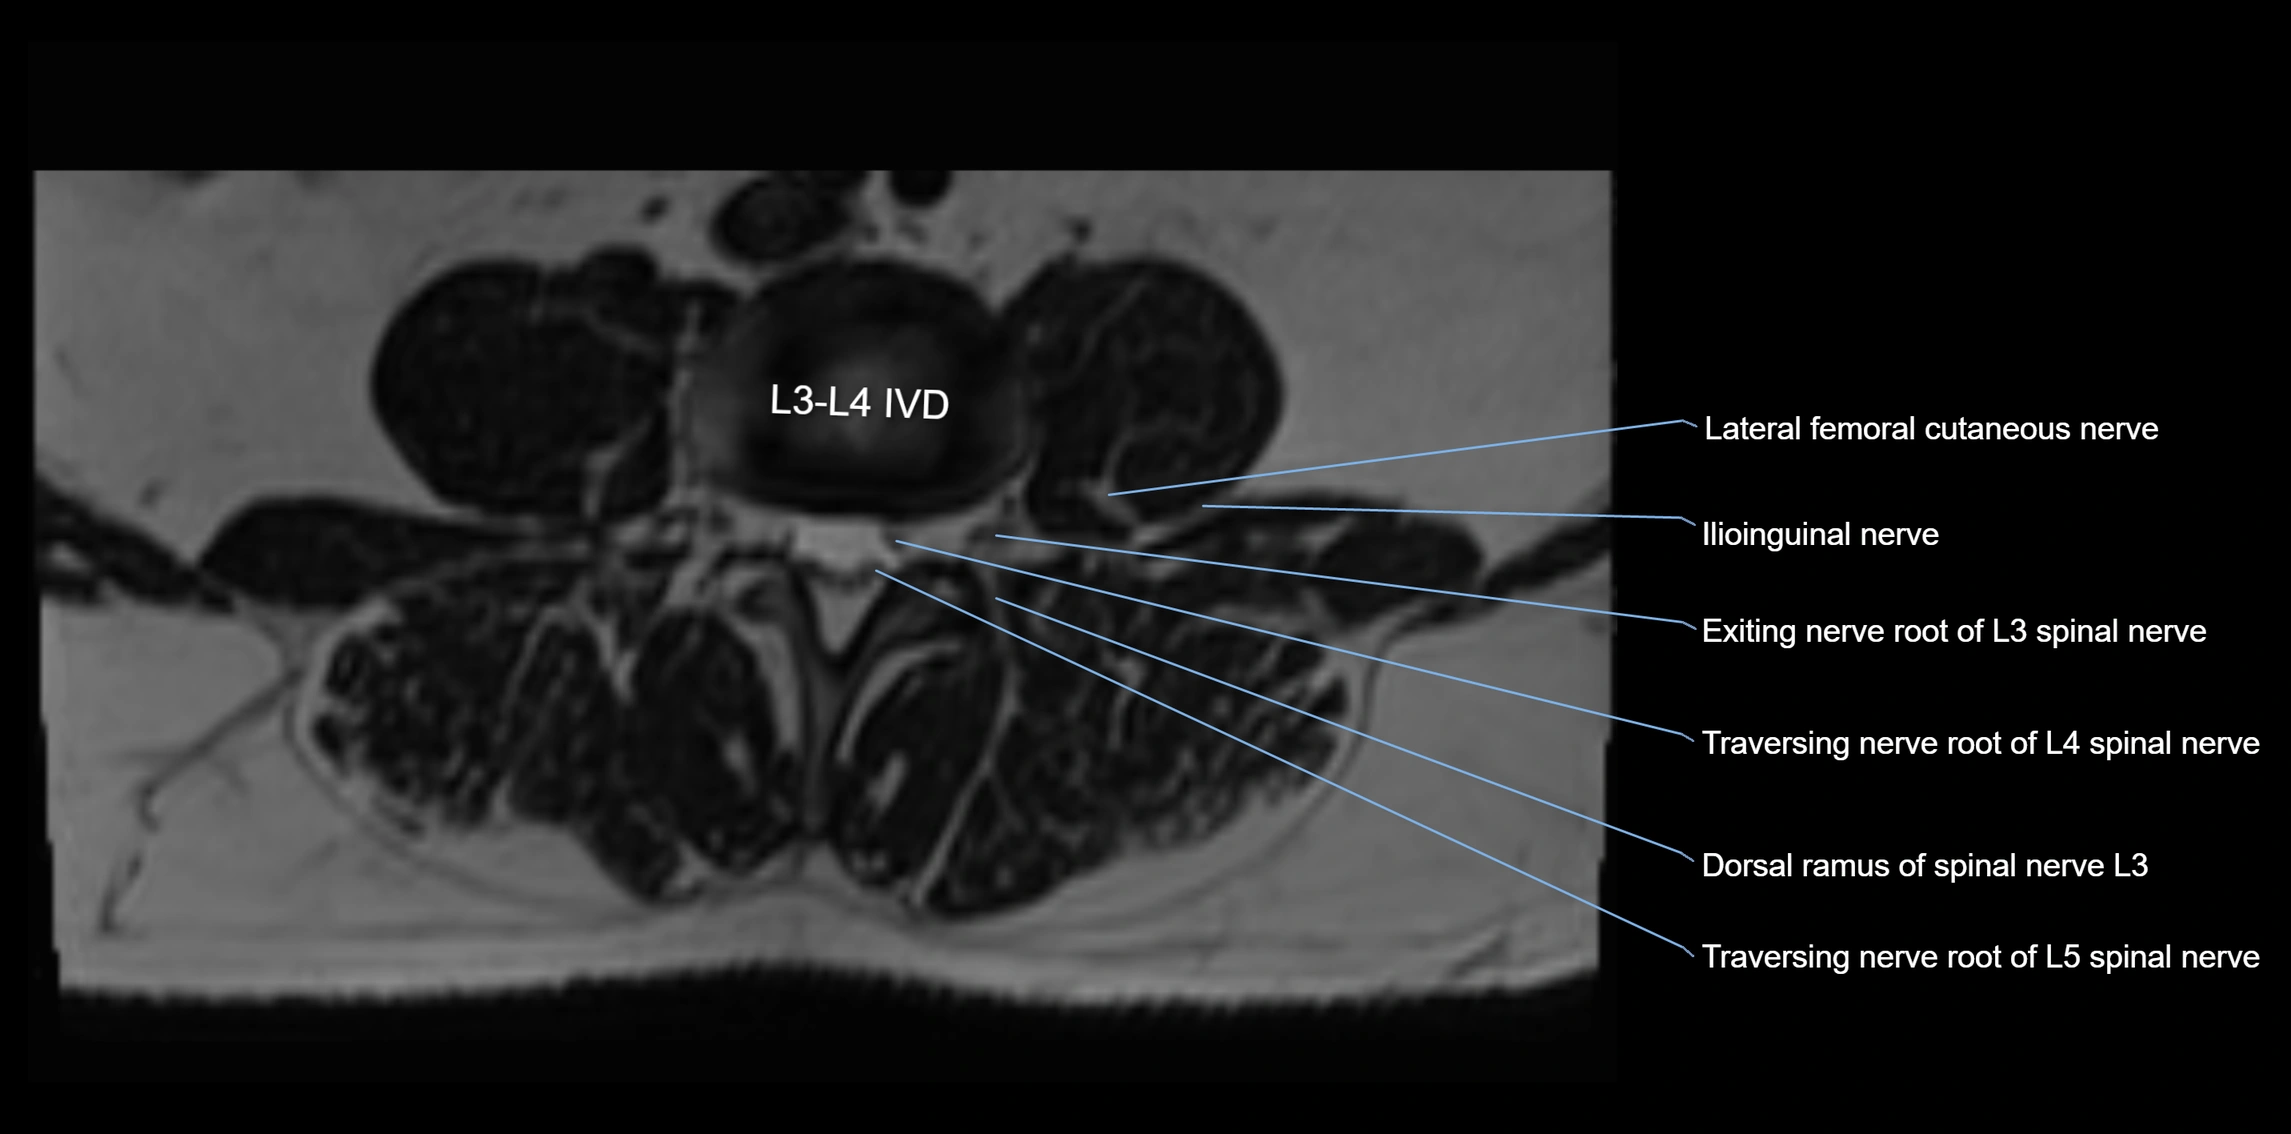

MRI image

image